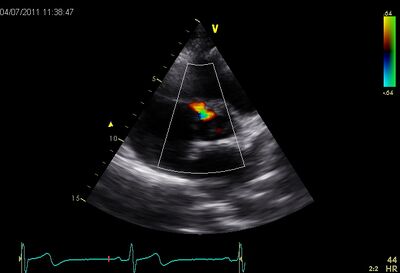

VSD09.jpg VSD10.jpg

Perimembraneus VSD PSAX Ao CW perimembraneus VSD PLAX